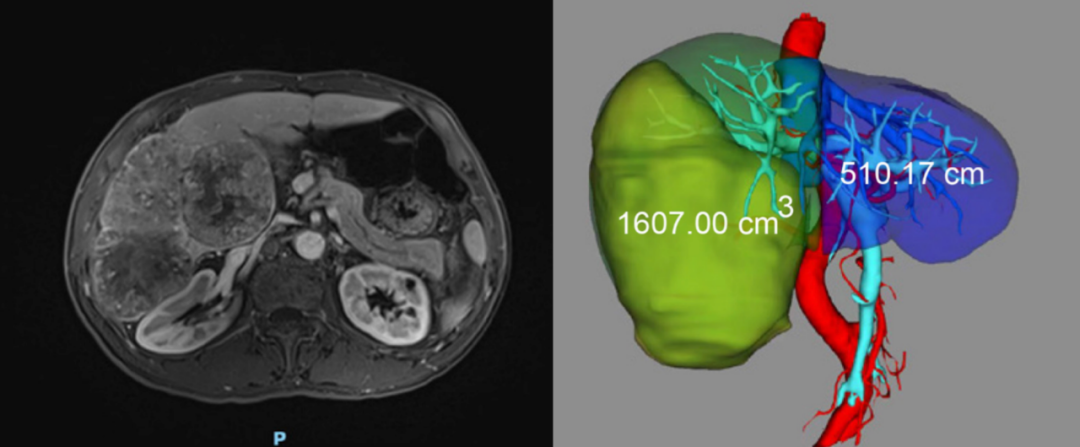

接受这次猪肝移植的是一位 71 岁的男性患者,确诊为乙肝肝硬化、肝右叶巨大肝细胞癌(HCC)。根据评估,患者无法耐受右叶切除术,经介入等治疗无效,随时可能出现破裂。因此,在充分征得家属、患者、和各方伦理委员会同意后,决定对这位患者开展异种辅助肝移植研究。

2024 年 5 月 17 日,手术由安徽医科大学第一附属医院孙倍成教授团队进行。由于患者右叶巨大肝癌,手术首先对这部分肿瘤进行切除。术中发现剩余的左侧肝脏无法满足肝癌患者的肝功能,决定供体猪的肝脏移植到患者右侧肝窝内。